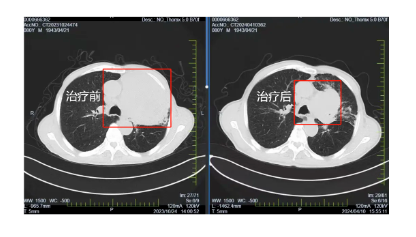

在國文醫(yī)院胸部腫瘤放化療Ⅲ病區(qū)醫(yī)護(hù)人員的精心照料和密切監(jiān)測下,患者經(jīng)過6周期的免疫治療,肺部腫瘤明顯縮小,一年間由原來的95x90mm降至70x50mm,腫瘤明顯縮小且腫瘤內(nèi)見壞死及空洞。張大爺?shù)纳眢w狀況也逐漸好轉(zhuǎn),原本因癌細(xì)胞壓迫導(dǎo)致的呼吸困難癥狀得到了明顯緩解,能夠進(jìn)行一些簡單的日?;顒?dòng),張大爺?shù)哪樕嫌种匦戮`放出笑容。